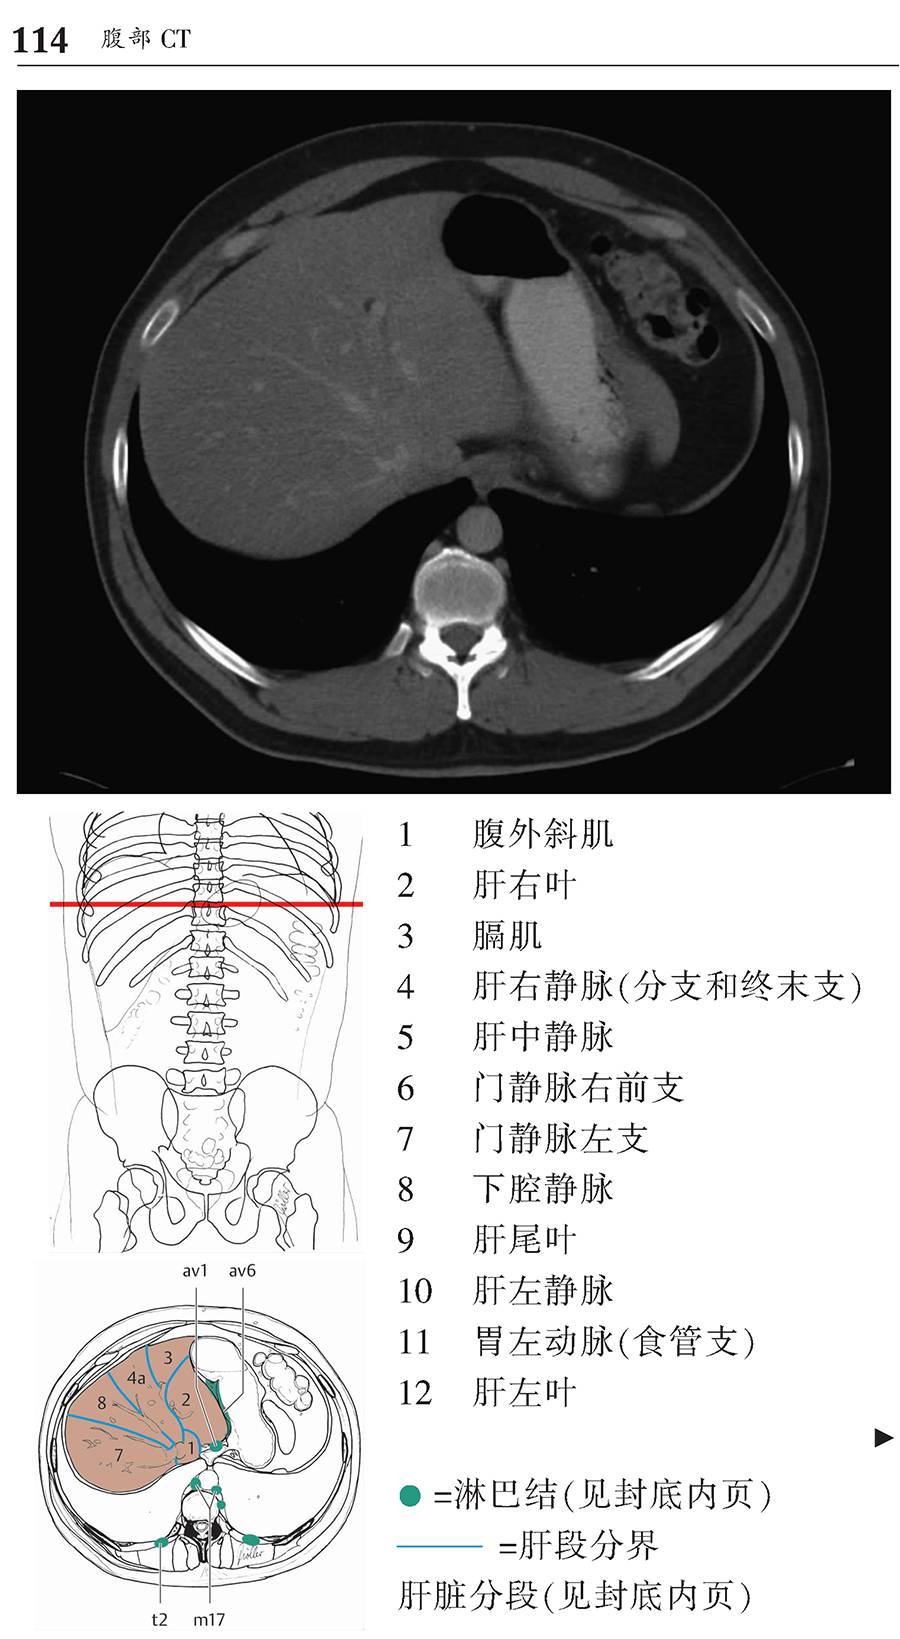

本书为断层解剖图谱,包括头颈部断层解剖,还包括脑部血管造影术,每一层面都包括精确的断层解剖和对应的彩色插图,左边页面为CT/MR图像,右边页面为对应的彩色手绘解剖示意图,便于学习和记忆!

1、版面采用教学式设计,2页为一个单元,左边页面为CT/MR图像,右边页面为对应的彩色手绘解剖示意图,并一一注明了解剖部位。

3、彩色手绘示意图中,各断层图像中同一个解剖结构均采用相同的颜色标注,便于识别。

书中全面、详细描述了每个CT/MR断层的解剖部位,图片清晰,浅显易懂,非常便于阅读和理解。书中每幅CT/MR图像都配有手绘的彩色示意图,示意图与影像图片高度匹配,通过示意图可以加深对CT/MR图像的理解,使CT/MR图像不再那么抽象难懂,同时也增加了学习的乐趣,不再感觉CT/MR图像的学习非常枯燥。本书内容全面、简洁易懂,是一本高质量的解剖图谱,非常适合影像诊断专业医师学习。

版面采用 教学式设计,2页为一个单元,左边页面为CT/MR图像,右边页面为对应的彩色手绘解剖示意图,并一一注明了解剖部位。

彩色手绘示意图中,各断层图像中同一个解剖结构均采用相同的颜色标注,便于识别。

l 胸部和腹部所有CT图像均为轴位、矢状位和冠状位三个层面图像。

l 封底折页内新增肺段、肝段和淋巴结分级。

腹部CT-横断面